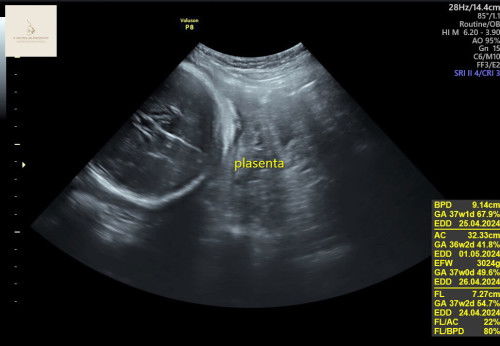

Placenta previa

Bun tadi saya kontrol di usia 37 week, minggu2 sebelumnya waktu cek placenta letaknya bagus kata dokter.. ini waktu 37 week posisi placenta ada yg diatas dan dibawah bun dekat kepala debayy dan 1 lilitan juga di jadwalin sc sama dokter tapi saya takut😩